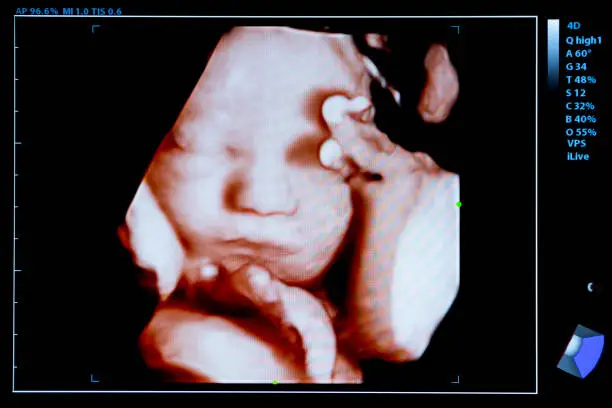

착상혈이 생리와 다른 가장 결정적인 요소는 바로 임신 가능성입니다. 착상혈은 임신이 시작되었음을 의미하는 신호일 수 있기 때문에, 출혈 후 며칠 내로 임신 테스트를 해보는 것이 필요합니다. 착상혈이 발생한 후에도 임신 초기 증상이 지속된다면, 테스트에서 양성 반응이 나올 확률이 높습니다. 그러나 착상혈을 생리로 잘못 생각해 임신 여부를 확인하지 않으면 혼란을 겪을 수 있습니다.

생리는 임신이 이루어지지 않았음을 의미하므로, 생리가 시작되었다면 임신 가능성은 거의 없습니다. 따라서 착상혈과 생리를 구분하는 데 있어 임신 테스트는 중요한 역할을 합니다. 착상혈이 의심된다면 생리 예정일 이후 적절한 시기에 임신 테스트를 통해 정확한 결과를 확인하는 것이 좋습니다.